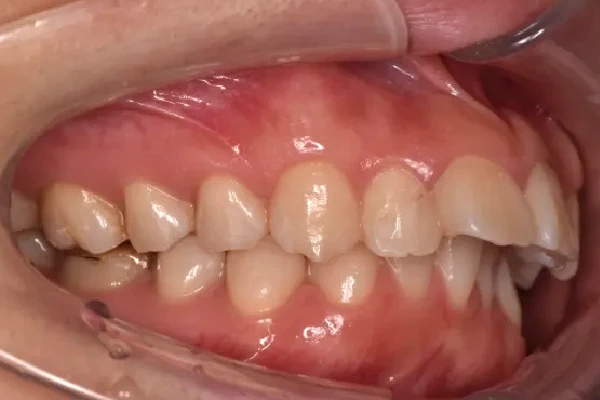

反対咬合

| 診断名・主訴 | 下顎前突、叢生 |

| 年齢・性別 | 23歳・女性 |

| 治療期間・回数 | 3年 |

| 治療に用いた主な装置 | 上顎5,5 下顎4,4 |

| 抜歯部位 | 舌側矯正 |

| 治療費 | 100万円(税抜) |

| リスク・副作用 | 装置による違和感・疼痛・歯肉退縮・歯根吸収・虫歯のリスクなど |

治療前